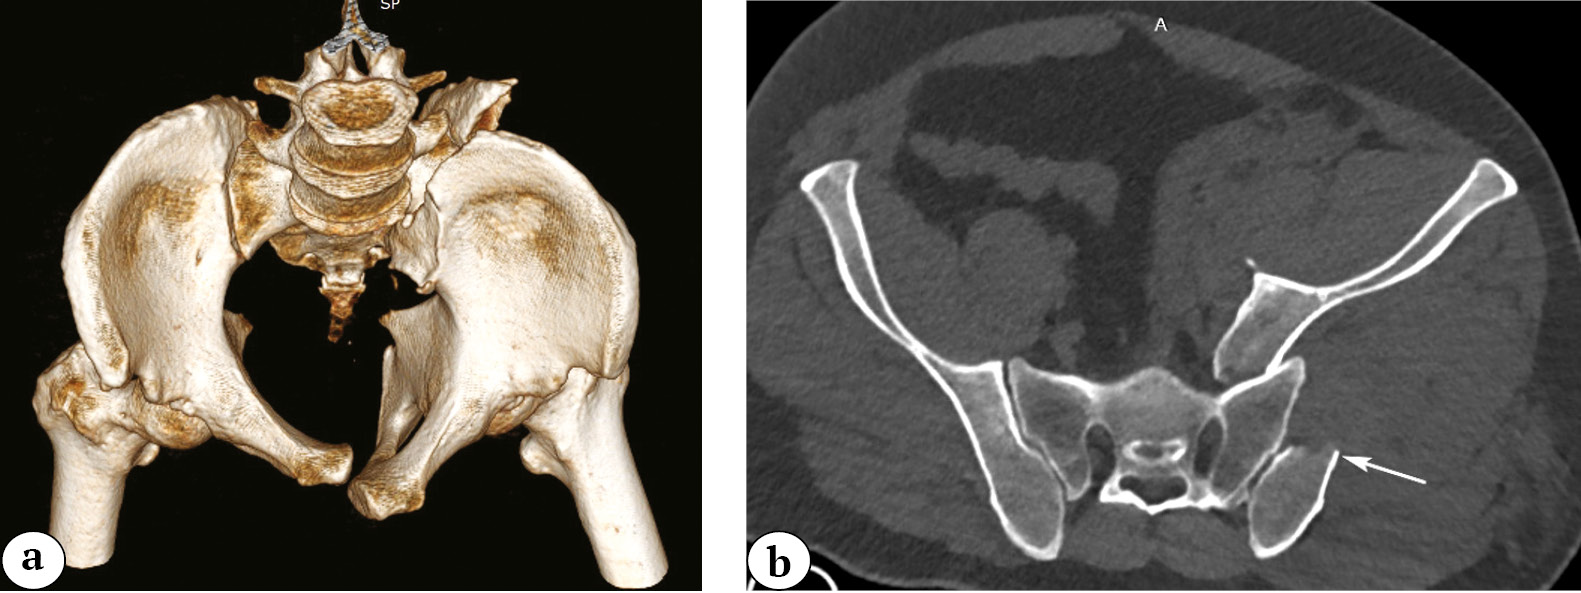

Through clinical observations and stress tests under anesthesia, we determined that vertical fractures are unstable and require surgical treatment, unlike horizontal fractures, which are relatively unstable. Vertical fractures can further be categorized into transverse and oblique. Transverse vertical fractures of the pubic bone’s base have their fracture plane predominantly oriented in the sagittal plane (Fig. 3).

Fig. 3. Vertical transverse fracture of the base of the pubic bone (the arrows indicate the fracture lines): a — 3D-CT image reconstruction; b — pelvic X-ray in the AP view

Another type of unstable vertical fracture of the base is the oblique fracture. In this case, the fracture line runs along the base of the pubic bone without affecting the symphysis, forming a distinctive sharp end of the fragment (Fig. 4). We propose to refer to such fractures as «longitudinal fractures of the pubic bone’s base.»

Fig. 4. Longitudinal fracture of the base of the pubic bone with a sharp ending: a — 3D-CT image reconstruction, the arrow indicates the sharp end of bone fragment; b — 2D-CT image reconstruction in the axial view, the arrows indicate the direction of the fracture along the base of the pubic bone